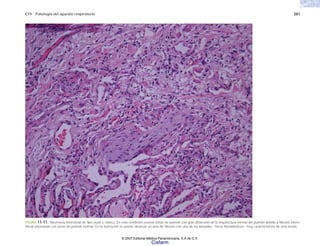

FIGURA 6-6. a)Cortehistológicoconneumoníanecrosanteconcoloniasbacterianas

porStaphylococcusHElOX.b)Coloniasbacterianasdecocosgrampositivos.Tinciónde

Gram 40x.